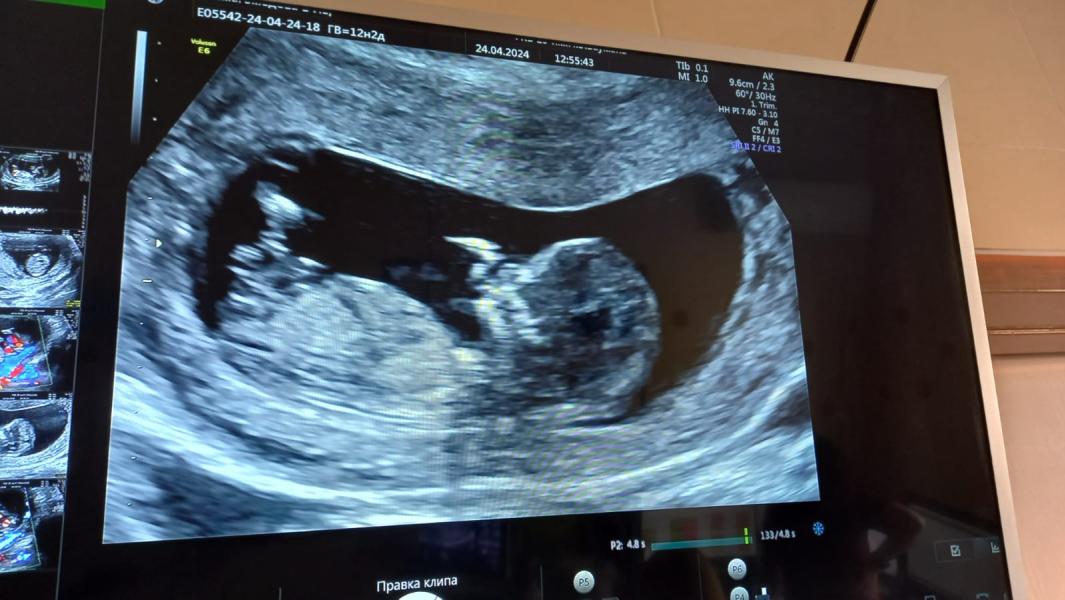

Кто там сидит?

Девочки , как думаете ,кто там сидит 🧐

Оказывается у сестры мальчик сидит в животе 😄🤓

12 недель? Мне именно с таким ракурсом не увидели пол на 16 неделе..

Да 12,